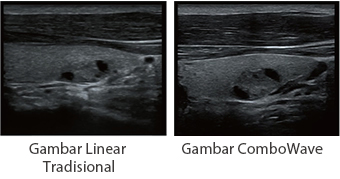

Transduser ComboWave

Dibandingkan dengan transduser tradisional, transduser ComboWave memanfaatkan tipe baru bahan piezoelektrik komposit untuk meningkatkan spektrum akustik dan mengurangi impedansi akustik. Dengan integrasi yang lebih erat dengan teknologi 3T unik dari Mindray, transduser linier ComboWave memungkinkan kinerja luar biasa dengan resolusi gambar yang tinggi dan uniformitas di tiroid, payudara, pembuluh darah, dan lainnya.